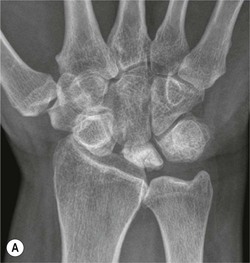

The scapholunate ligament is most frequently involved. Radiographs may show scapholunate diastasis (>3 mm). The lunate demonstrates dorsal rotation on lateral views and volar rotation of the scaphoid. This results in an increase in the scapholunate angle (>60°) known as dorsal intercalated segment instability (DISI) (Fig. 46-27). A DISI deformity of the carpus may also be associated with fractures of the scaphoid.

Disruption of the lunotriquetral ligament is less common. In this situation there is volar rotation of the lunate on lateral radiographs, with reduction of the scapholunate angle (<30°). On PA radiographs there may be an obvious step between the distal articular surface of the lunate and triquetrum. This is termed volar intercalated segment instability (VISI).

More subtle degrees of instability may be demonstrated by an instability series of radiographs acquired with radial and ulnar deviation and with a clenched fist view. Video fluoroscopy is also useful for assessing dynamic wrist instability.